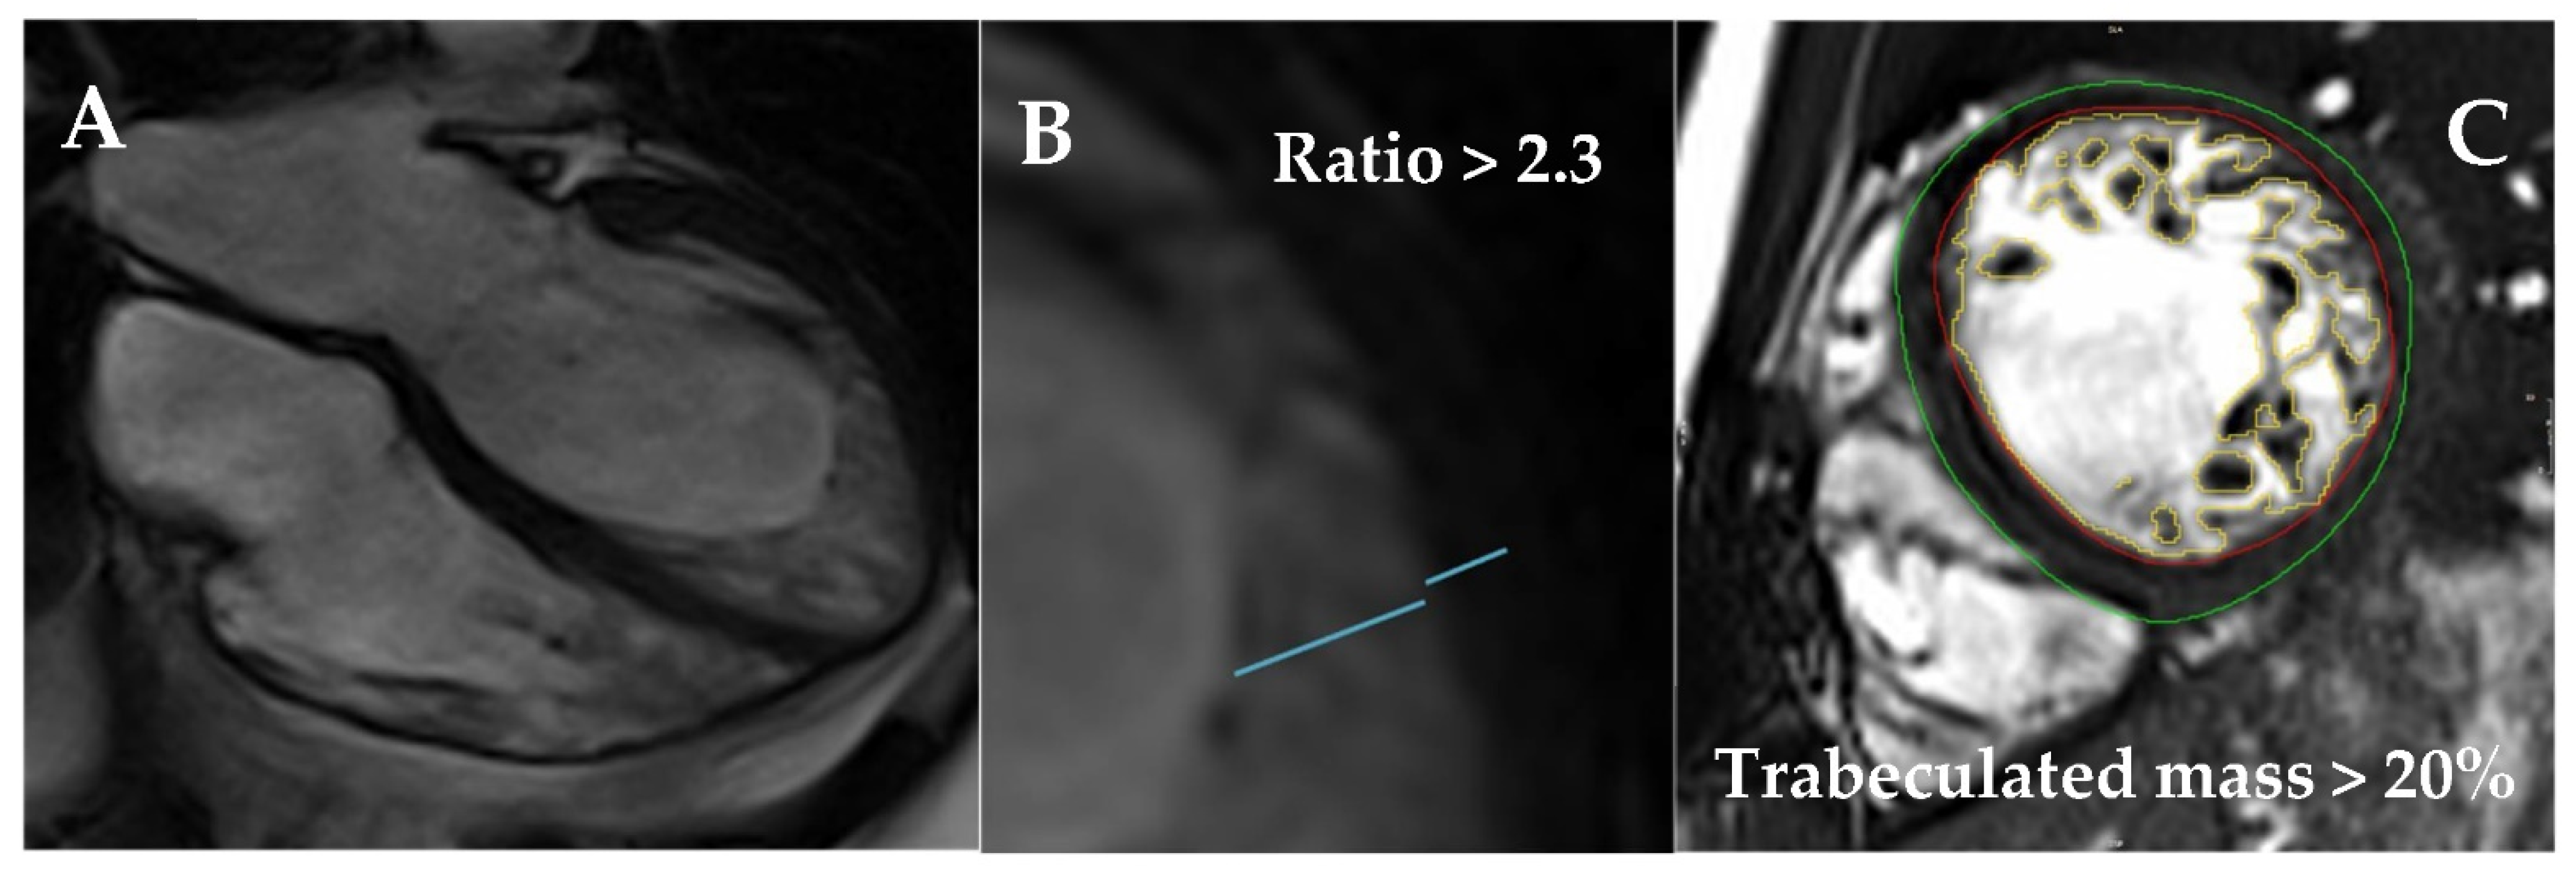

6. Left Ventricular Noncompaction

- Towbin, J.A.; Lorts, A.; Lynn, J. Left ventricular non-compaction cardiomyopathy. Lancet 2015, 22, 813–825. [Google Scholar] [CrossRef]

- Chin, T.K.; Perloff, J.K.; Williams, R.G.; Jue, K.; Mohrmann, R. Isolated noncompaction of left ventricular myocardium. A study of eight cases. Circulation 1990, 82, 507–513. [Google Scholar] [CrossRef] [Green Version]

- Oechslin, E.N.; Attenhofer Jost, C.H.; Rojas, J.R.; Kaufmann, P.A.; Jenni, R. Long-term follow-up of 34 adults with isolated left ventricular noncompaction: A distinct cardiomyopathy with poor prognosis. J. Am. Coll. Cardiol. 2000, 36, 493–500. [Google Scholar] [CrossRef] [Green Version]

- Petersen, S.E.; Selvanayagam, J.B.; Wiesmann, F.; Robson, M.D.; Francis, J.M.; Anderson, R.H.; Watkins, H.; Neubauer, S. Left Ventricular Non-Compaction: Insights From Cardiovascular Magnetic Resonance Imaging. J. Am. Coll. Cardiol. 2005, 46, 101–105. [Google Scholar] [CrossRef] [PubMed] [Green Version]

- Jacquier, A.; Thuny, F.; Jop, B.; Giorgi, R.; Cohen, F.; Gaubert, J.-Y.; Vidal, V.; Bartoli, J.M.; Habib, G.; Moulin, G. Measurement of trabeculated left ventricular mass using cardiac magnetic resonance imaging in the diagnosis of left ventricular non-compaction. Eur. Heart J. 2010, 31, 1098–1104. [Google Scholar] [CrossRef] [PubMed] [Green Version]

- Captur, G.; Muthurangu, V.; Cook, C.; Flett, A.S.; Wilson, R.; Barison, A.; Sado, D.M.; Anderson, S.; McKenna, W.J.; Mohun, T.J.; et al. Quantification of left ventricular trabeculae using fractal analysis. J. Cardiovasc. Magn. Reson. 2013, 15, 36. [Google Scholar] [CrossRef] [PubMed] [Green Version]

- Zemrak, F.; Ahlman, M.A.; Captur, G.; Mohiddin, S.; Kawel-Boehm, N.; Prince, M.; Moon, J.; Hundley, W.G.; Lima, J.A.; Bluemke, D.; et al. The Relationship of Left Ventricular Trabeculation to Ventricular Function and Structure Over a 9.5-Year Follow-Up. J. Am. Coll. Cardiol. 2014, 64, 1971–1980. [Google Scholar] [CrossRef] [Green Version]